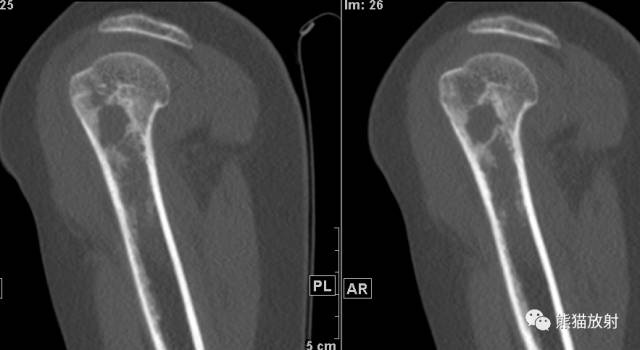

II型及III型 ↓ 肱骨上段Ewing肉瘤(男7岁)

↓ 肱骨上段ABC(男7岁)